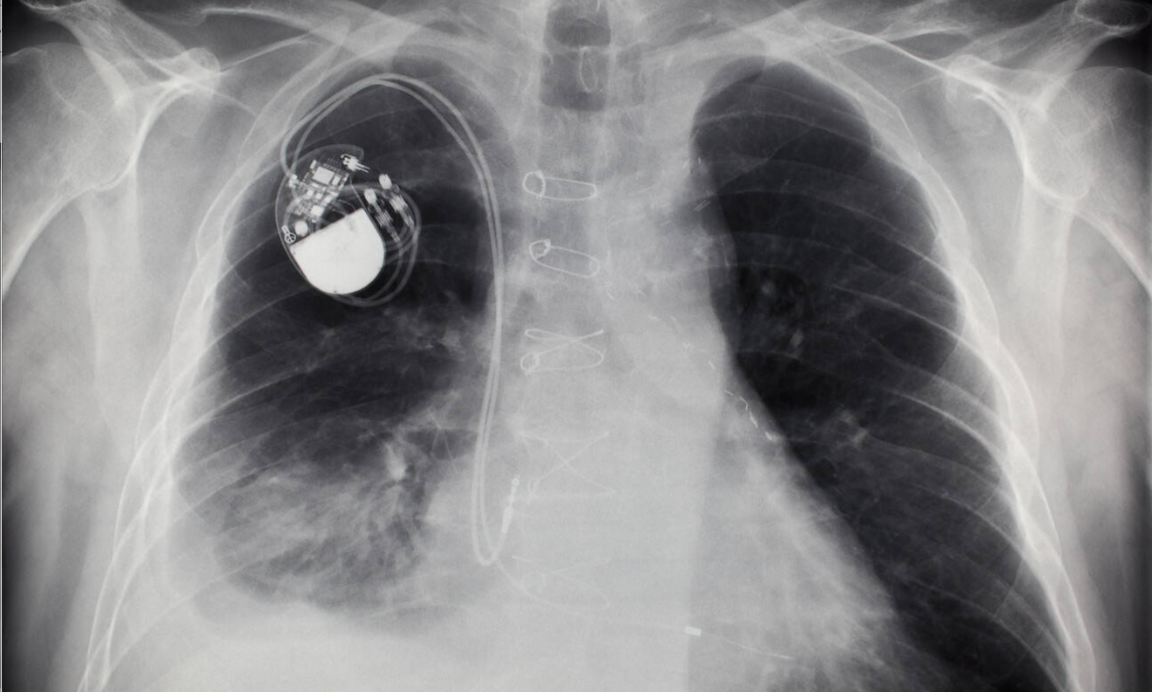

How does property law affect implanted medical devices?

When an implanted medical device stops working, who is legally responsible? Professor Murieann Quigley's research helps to answer this.